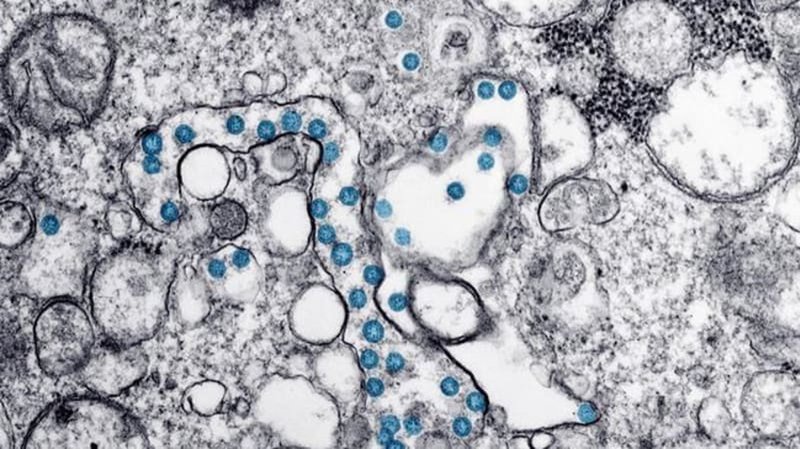

The latest numbers of confirmed and presumptive COVID-19 cases in Canada as of 6:15 a.m. ET on June 26, 2020: